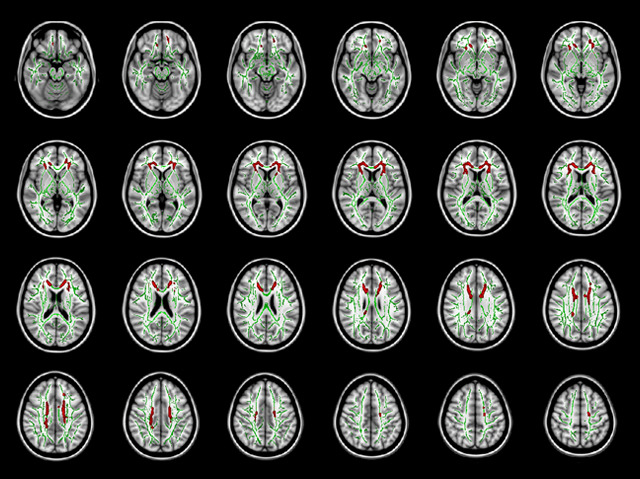

The internet depends on a vast network of fibre optic cables that ferry the billions of parcels of data around the globe. It’s an unfortunate irony therefore that internet addiction – an affliction made possible by these information pathways – appears to damage the brain's own fibre network. In online addicts, the biological bridges that link different brain areas, called white matter, are significantly reduced (indicated by red areas in these brain maps) in zones associated with mediating craving and compulsive behaviours. Without these areas functioning properly, resisting the urge to log on becomes even more difficult. Finding ways to protect or regenerate white matter could provide a potential new treatment target for internet addiction, which is a growing problem. Prevalence rate estimates vary greatly but some think that 8% of the population in Europe and North America are affected, with even higher rates in Asia.